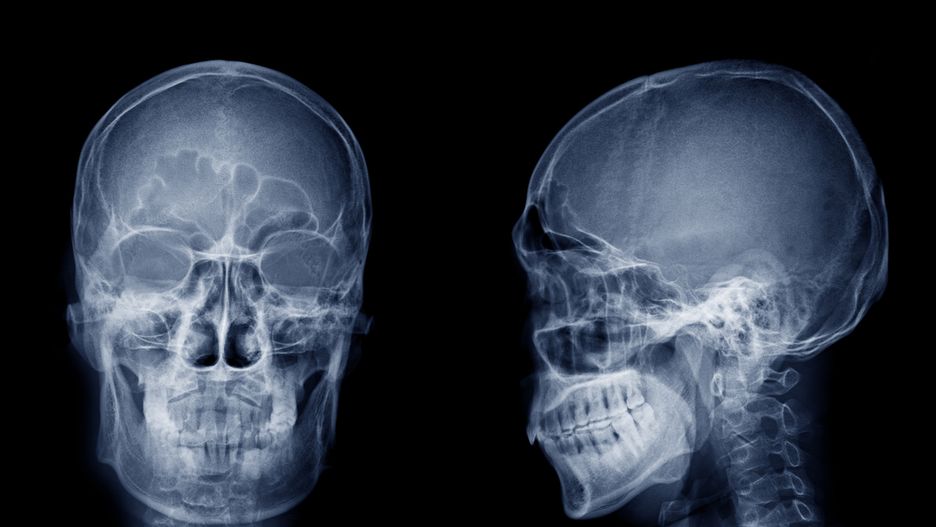

Czaszka to struktura kostna lub chrzęstna. Stanowi szkielet głowy, a jej główną funkcją jest osłona mózgu i innych narządów, które znajdują się w głowie, w tym również początkowych odcinków układu pokarmowego i oddechowego. Można wyróżnić dwie jej części: mózgoczaszkę i twarzoczaszkę.

Mózgoczaszka ma kształt kulisty i złożona jest z dwóch części: sklepienia i podstawy. Ma za zadanie chronić mózg i narządy zmysłów. Mózgoczaszkę tworzą kości: potyliczna, czołowa, ciemieniowa, skroniowa, sitowa oraz klinowa.

Twarzoczaszka umiejscowiona jest z przodu głowy, dookoła jamy gębowej i gardzieli. Otacza przednią część przewodu pokarmowego. Zabezpiecza przed urazami narządy zmysłów: wzroku, węchu i smaku. Zbudowana jest z kości nosowych, łzowych, małżowin nosowych dolnych, lemiesza, szczęk, żuchwy, kości podniebiennych, jarzmowych oraz kości gnykowej. W przeciwieństwie do mózgoczaszki posiada elementy ruchome. To żuchwa, w której znajdują się zęby oraz kość gnykowa.